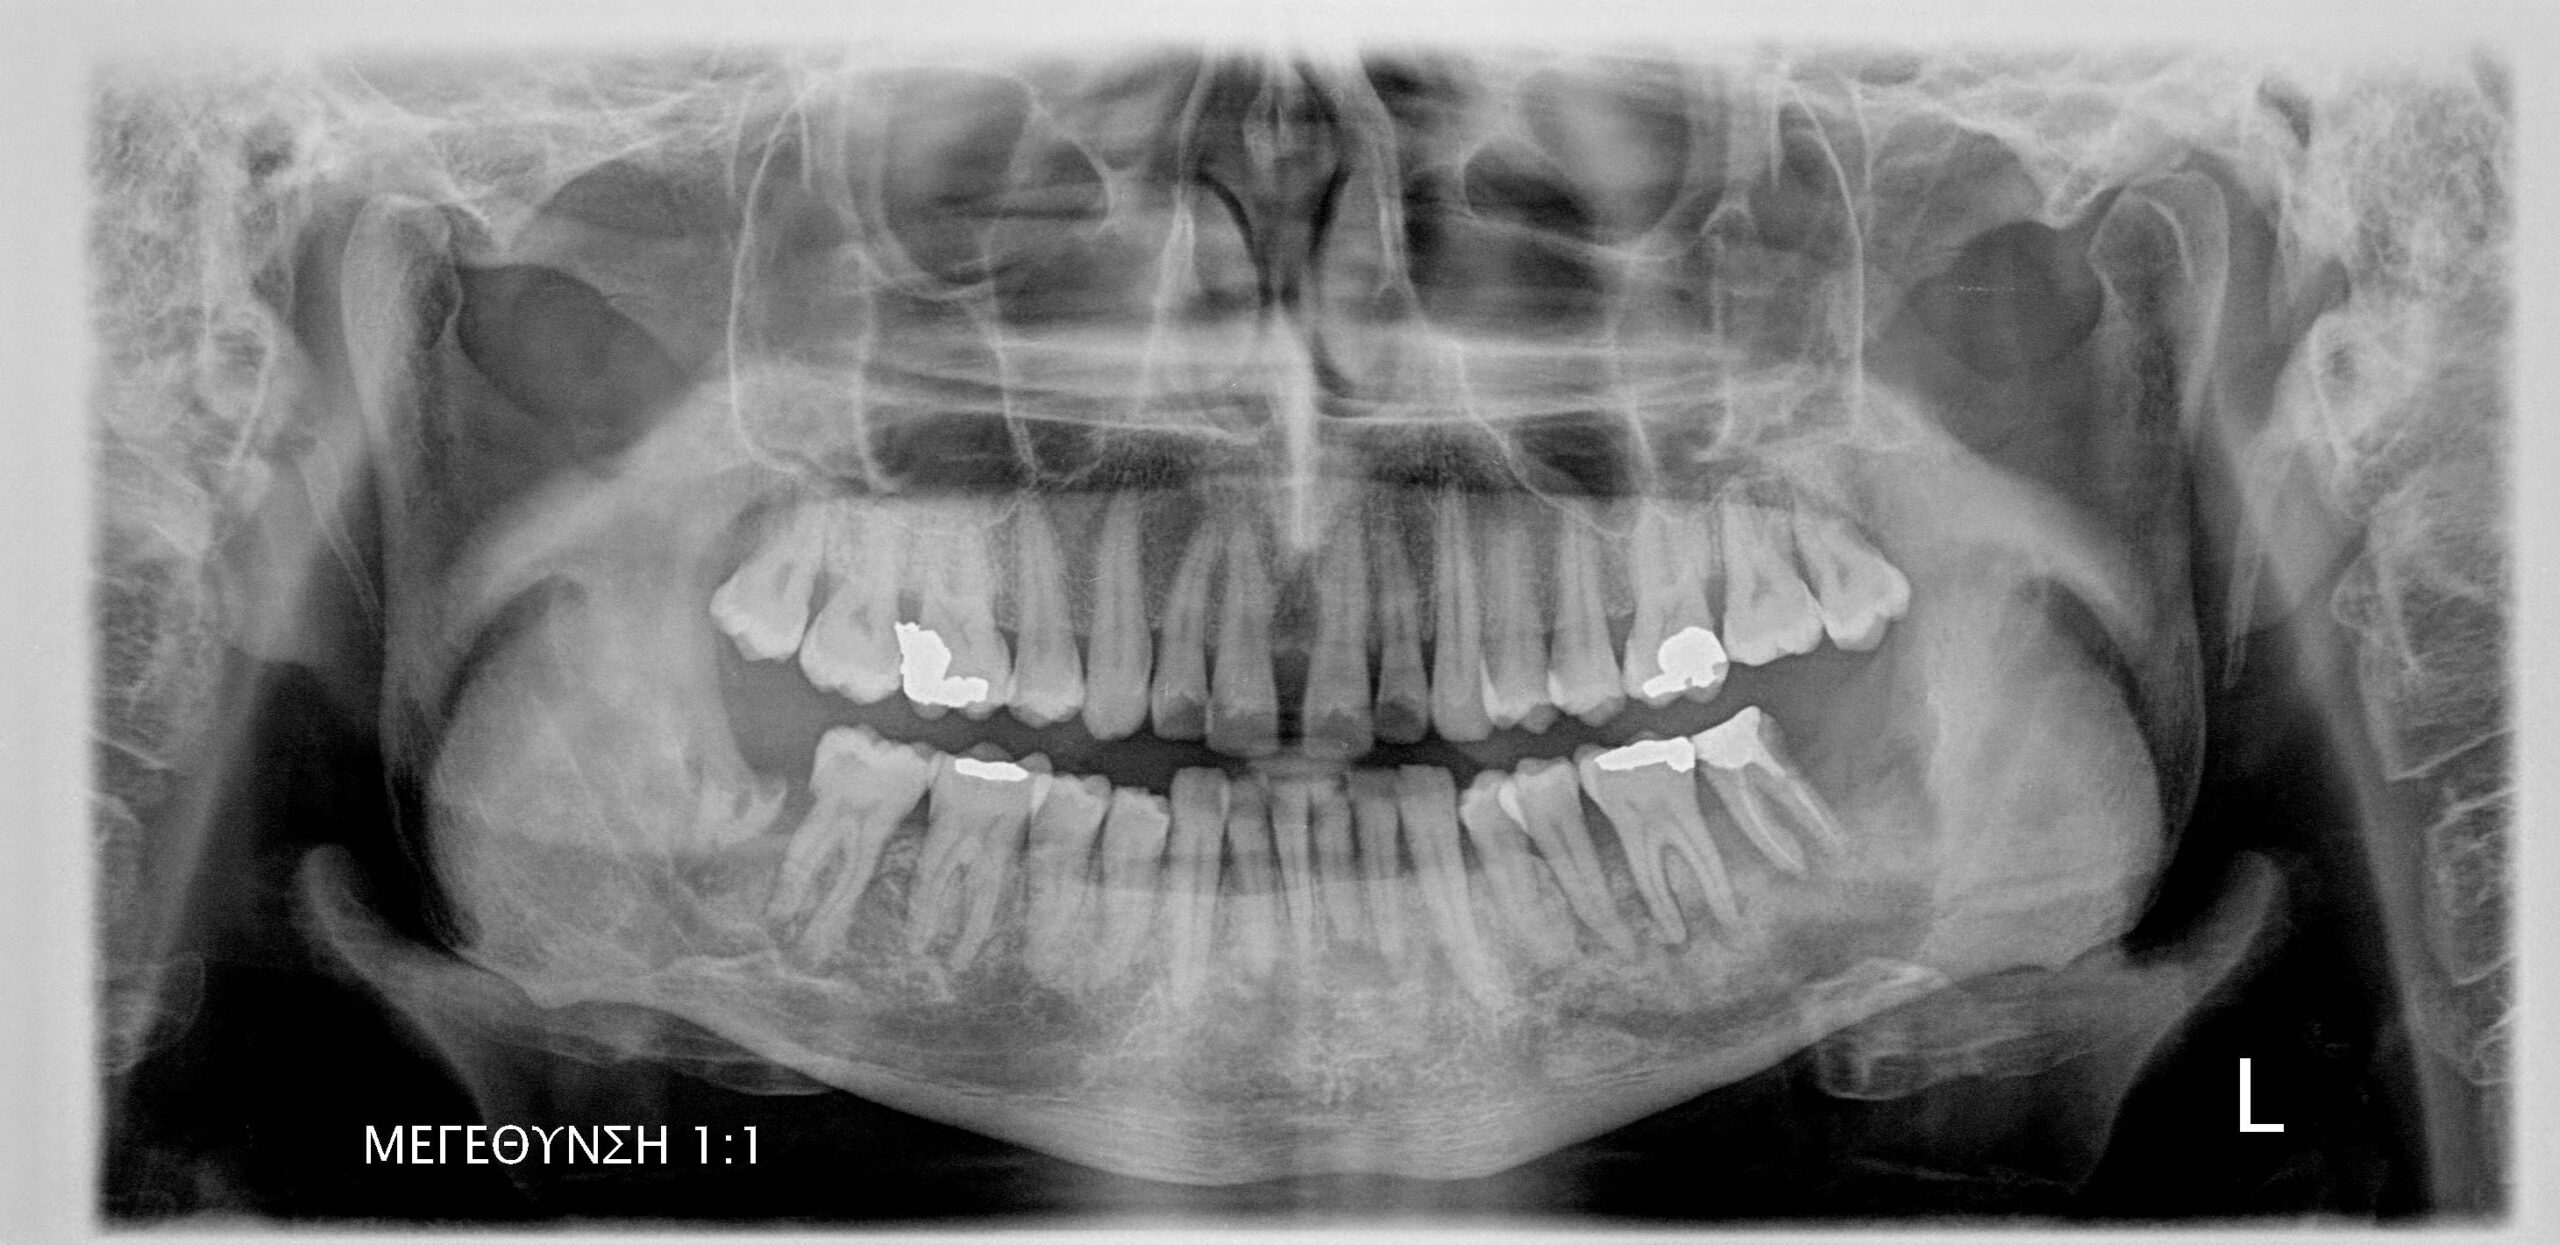

- Ακτινογραφικά ευρήματα: Παρατηρείται διάχυτη οστεολυτική βλάβη με ασαφή και σκοροφαγωμένα όρια, η οποία προκαλεί λύση και διάτρηση των συμπαγών πετάλων της γνάθου, καταλαμβάνοντας μεγάλο μέρος του σπογγώδους οστού. Συχνά οι βλάβες απεικονίζονται ως μικτές με την παρουσία οστικών απολυμάτων εντός των οστεολυτικών βλαβών. Σε προχωρημένα στάδια η βλάβη μπορεί να προκαλέσει παθολογικό κάταγμα της γνάθου.